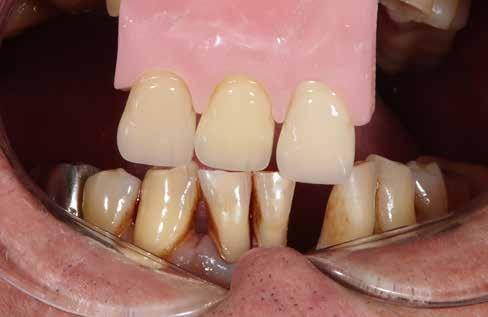

A felső frontfogak állapota elhanyagolt, a parodontális struktúrák részben erősen károsodottak, VMK korona az 12 zónában, az ínyszél szürke, fekete approximális háromszögek… vörös-fehér esztétikáról nem is beszélhetünk (1. kép). Így jelentkezett a hölgypáciens a Weston Dental Specialists Group rendelőben. Elvárásai magasak voltak. A defektusok kezelését, a gingiva lefutásának korrigálását kívánta. Gyorsan világossá vált, hogy a megoldást csak a négy frontfog teljes kerámiakoronával való ellátása jelentheti. A jelen eset bemutatja, hogy az IPS e.max ZirCAD Prime segítségével hogyan lehet tiszta, tetszetős és esztétikus mosolyt létrehozni.

1. kép: Kiindulási helyzet.